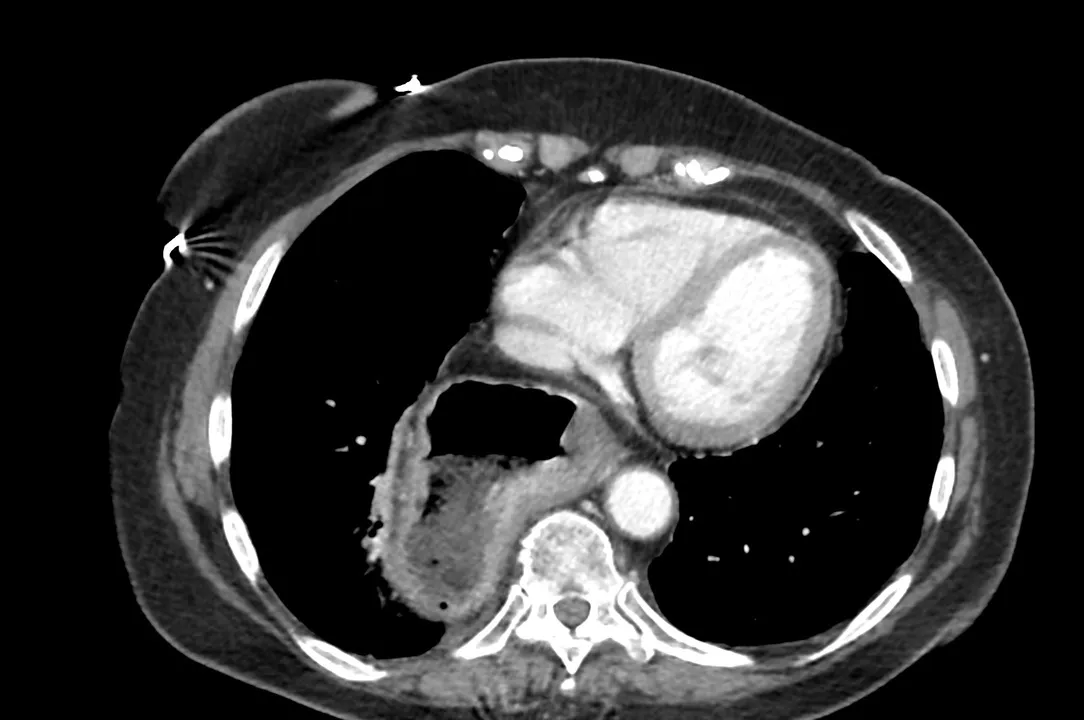

Ernia iatale : Un gran numero di pazienti affetti da GERD può avere un’ernia iatale che non causa necessariamente sintomi di esofagite.

TAC di un’ernia iatale